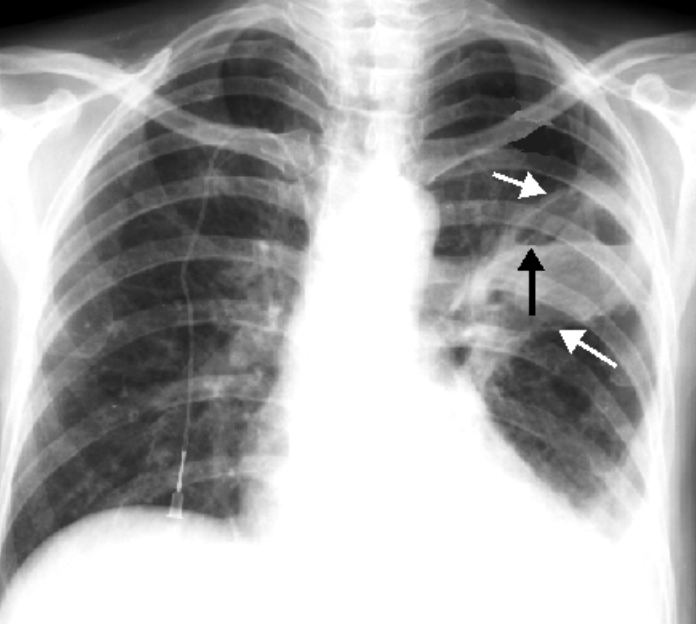

Trong đó, chụp X quang là kỹ thuật chẩn đoán hình ảnh đầu tay, cơ bản và có giá trị cho phép quan sát tổn thương bên trong phổi. Bác sĩ sẽ sử dụng máy chụp X quang để phát ra tia X – là tia có bước sóng ngắn với khả năng đâm xuyên mạnh để đi qua các tế bào mô mềm và dịch, từ đó thu được hình ảnh của phổi.

Với kỹ thuật này, trên hình ảnh X quang viêm phổi tụ cầu cho thấy xuất hiện nhiều ổ viêm (những đám mờ màu trắng) có hình tròn, không đều nhau về mặt kích thước và không đối xứng hai bên phổi. Ngoài ra, khi thực hiện cấy đờm, máu, dịch màng phổi sẽ thấy sự xuất hiện của các vi khuẩn tụ cầu.

- Chụp X quang viêm phổi tụ cầu là một trong những phương pháp chính được thực hiện để chẩn đoán phát hiện bệnh bên cạnh các xét nghiệm máu, dịch đờm. Hình ảnh chụp được sẽ cho thấy các ổ viêm ở hai bên phổi do tụ cầu khuẩn gây ra với hình dáng tròn không đều và không đối xứng.